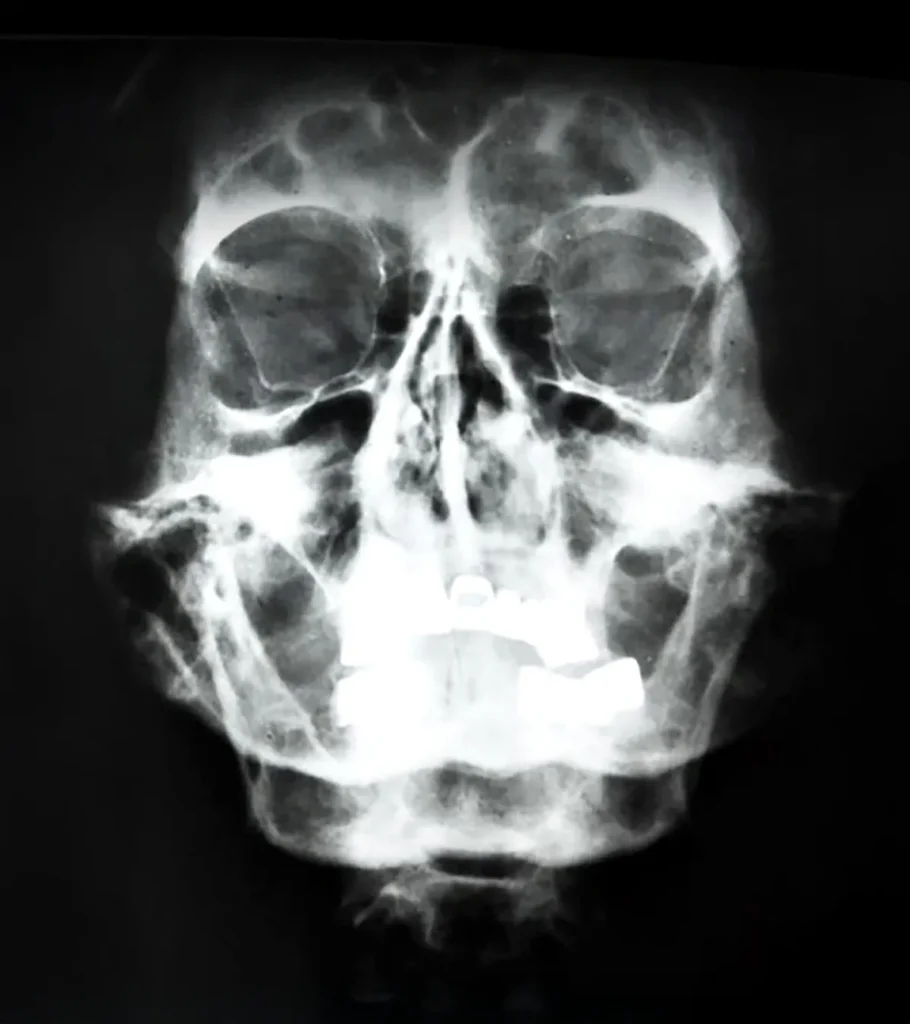

Podemos resumirlo así: un hipocondriaco paranoico, con severos problemas gastrointestinales que le impedían ir al baño durante semanas, con eccemas persistentes en las extremidades, medio sordo después de que le reventara cerca una bomba en las trincheras de la Gran Guerra, insomne crónico y enfermo de Parkinson, vio agravadas todas aquellas dolencias por un médico charlatán de tercera categoría en los compases finales de la II Guerra Mundial, cuando dirigía personalmente a los ejércitos alemanes contra formidables enemigos como la URSS o los aliados desembarcados en Normandía.

Desde que Hitler conoció en los años 30 a Morell, un especialista en enfermedades venéreas, gracias a la mediación del fotógrafo Heinrich Hoffman, la salud del Führer no dejó de deteriorarse paulatinamente, asegura el autor de El paciente A: «Es Theodor Morell quien hace enfermar cada vez más a Hitler y le convierte en un adicto a las drogas. Le administraba hasta 70 medicamentos habituales que consignaba en un calendario: metanfetaminas, cocaína tópica, testosterona, glucosa, estradiol, corticosteroides, píldoras para dormir… Los jerarcas nazis sospechaban que algo no iba del todo bien pero no se atrevían a hacer nada porque Morell era un privilegiado. El único, por ejemplo, que veía a Adolf Hitler, que era muy pudoroso, desnudo«.

Un asunto que nunca pasa de moda y que seguramente ustedes estaban esperando: los genitales del Führer. Muchas veces se ha dicho que le faltaba un testículo y en El paciente A se postula un posible hipospadias, o deformación de la uretra. Por otra parte, no deja de resultar extraño que Morell le inyectara a testosterona. ¿Fueron los complejos sexuales de aquel hombre, tal vez sifilítico e impotente, los que llevaron al mundo al desastre?